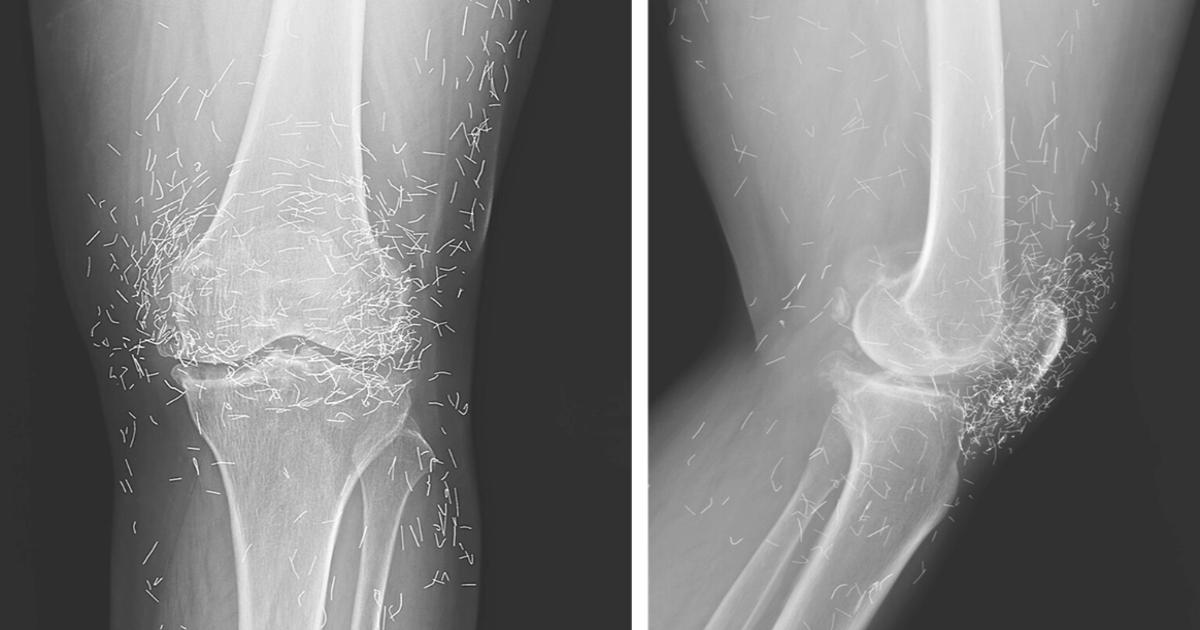

Una radiografia ha mostrato ciò che i medici non si aspettavano: un vero e proprio mosaico di minuscoli fili metallici nelle ginocchia, insieme a ispessimenti ossei e segni evidenti di danno articolare. I medici hanno spiegato che l’agopuntura con oro non solo non ha alcuna prova scientifica di efficacia, ma può risultare pericolosa.

I fili d’oro possono infatti migrare all’interno del corpo, causare cisti o lesioni ai tessuti, e rendere rischiose le risonanze magnetiche, poiché il metallo potrebbe spostarsi danneggiando i vasi sanguigni. Insomma, un trattamento che promette di alleviare il dolore, ma rischia di farne molto di più.